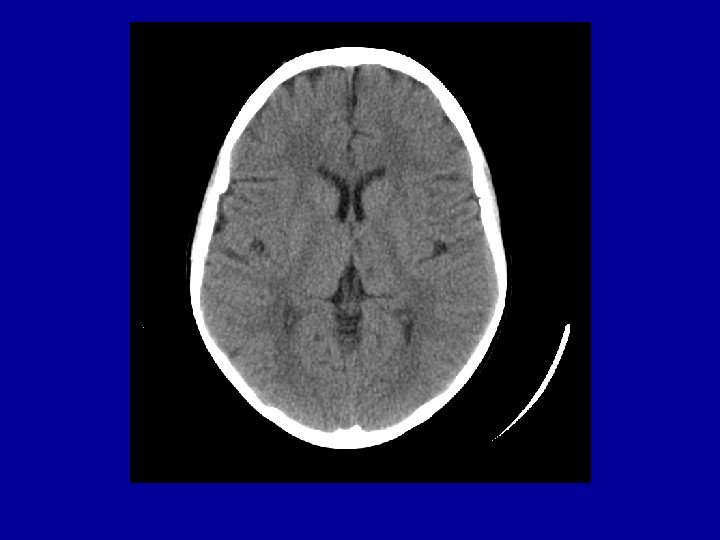

Investigations • • CXR: mild cardiomegaly Hgb 73 WBC 16. 0 => 9 to 12 in hospital Plt 529 CBG: p. H 7. 41 p. CO 2 38 p. O 2 191 Lytes N INR 1. 2 PTT 23 Type and screen done CT head done immediately and “normal”

Course in Hosp • Resolution of most of her neurologic findings within a few hours • I phoned neurology after my shift and they had not been consulted yet • Hematology consulted later in day • ECHO and ECG confirmed mild rt and left ventricular enlargement and norm ventricular func • MRI/MRA done and abnormal

MRI (FLAIR) vs. CT